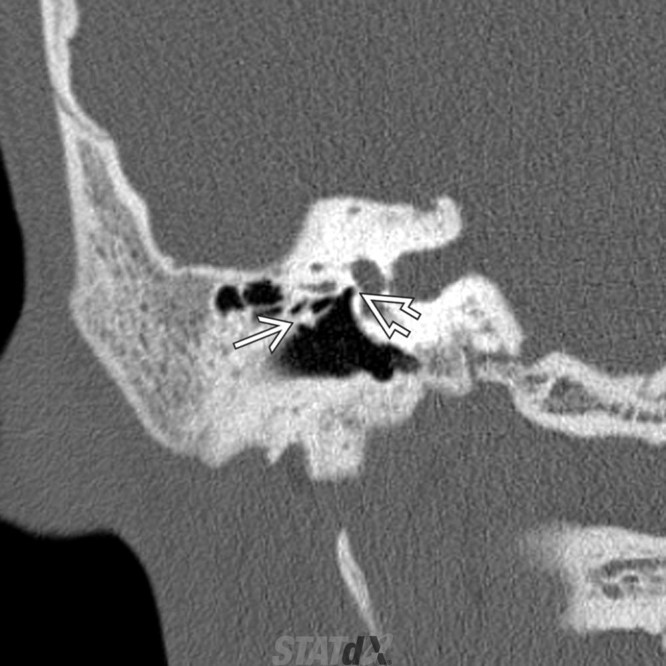

Congenital External and Middle Ear Malformation

**Tympanic segment of the facial nerve will always be aberrant in the location of the oval window instead of inferior to the lateral semi-circular canal

Prolapsing facial nerve (protruding intratemporal facial nerve)

Tubular soft tissue prolapsing into oval window niche from undersurface of LSC. Caused by dehiscence of bony covering of the facial nerve.

No enhancement! If enhances then it is a Schwannoma.

May project into oval indow.